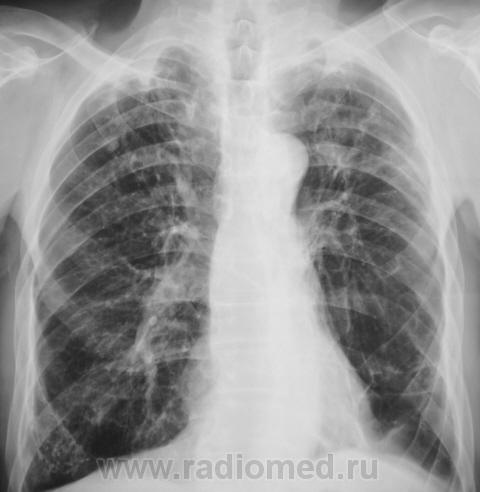

Болел, давно снят с учета. Клиническое излечение. Рецидив?

Рентгенограмма.